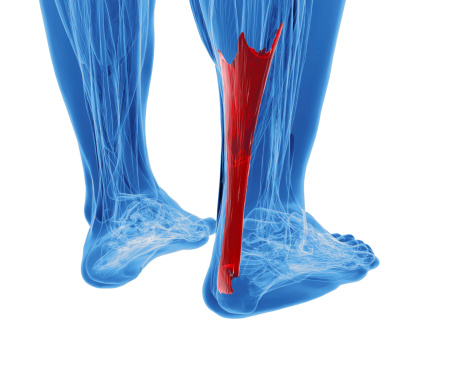

La sindrome dell’anca a scatto, nota anche come anca del ballerino è una condizione in cui si ha la sensazione di uno “scatto” quando si fa un particolare movimento, come durante una corsa, quando ci si alza da una sedia o semplicemente camminando. Spesso si sente anche un vero e proprio rumore. E’ un qualcosa di abbastanza comune che solitamente non comporta complicanze, ma chi utilizza molto tale articolazione, magari perché è un atlta, un ballerino o sta molte ore in piedi, può arrivare ad essere condizionato da debolezza e dolore che interferiscono con le prestazioni. Ecco cosa occorre sapere al riguardo.